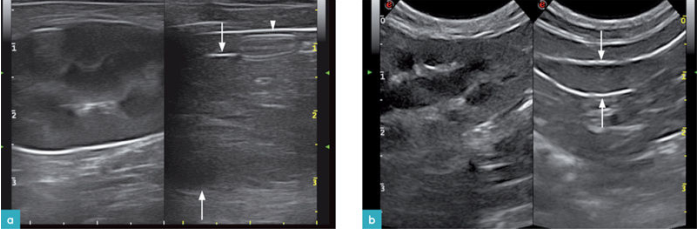

肝脏和脾脏的解剖学关系,使得我们可以把肾脏回声和邻近的器官相比较。肾皮质通常对肝脏是等回声或低回声的,对脾脏是低回声的(图3)。

超声波清楚地区分了低回声的肾髓质和皮质的回声波,由于肥胖猫的皮质的脂肪浸润,所以其回声会增强。在健康猫中,由于近端小管的脂肪增加(以液泡的形式),尤其是公猫,所以肾皮质回声会增加。

骨盆凹陷将髓腔分隔,其旁运行小叶间血管。由于肾盂上存在脂肪以及纤维组织,所以肾盂呈现高回声带,并偶尔会出现声影,宽度约为1-2 mm。肾顶部是肾髓质的延伸,并连接着肾盂。肾顶部被肾窦所围绕,而肾窦含有脂肪组织,因此为高回声带,且这一特点在肥胖的猫尤其显著。。使用高频探头可以在肾门处看到肾静脉,但是由于动脉太小很难观察到动脉。肾被膜在肾脏的最外围的区域显示为高回声线 (图4.视频 1)。健康动物的肾脏是没有液体围绕的。